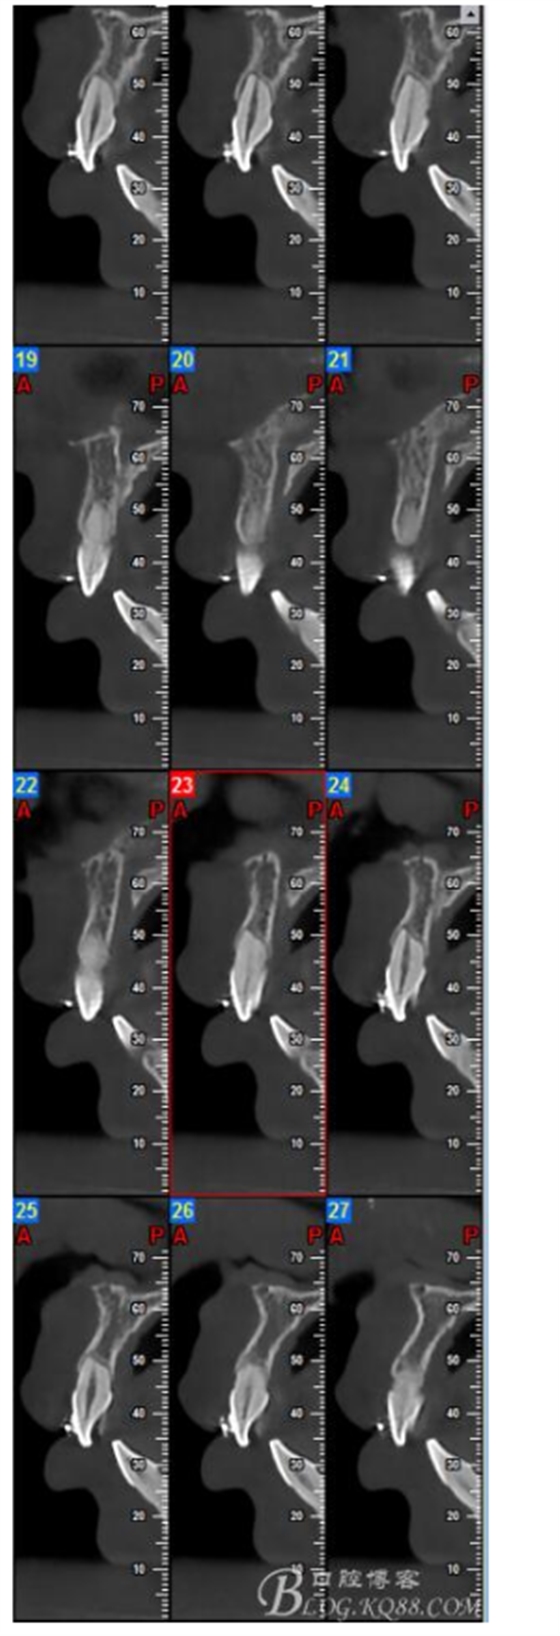

大多數(shù)研究認(rèn)同牙根再吸收的嚴(yán)重性與正畸治療的持續(xù)時間、力量大小相關(guān)。臨床醫(yī)師應(yīng)該采用輕力、高效的矯治手段進行正畸治療,并在正畸治療前、中、后進行X線檢查對比,觀察牙根再吸收的發(fā)生情況。研究發(fā)現(xiàn):間斷治療的患者其牙根再吸收量明顯少于那些持續(xù)治療的患者。應(yīng)用力的中斷有助于已破壞的牙周組織重建并減少牙根的進一步縮短。